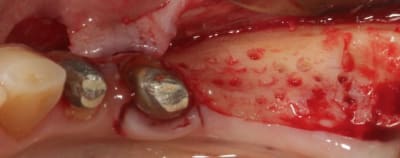

Cas 1-coté gauche maintenant:

1- ouverture, forme et configuration différente

2- une fois échauffée avec le coté droit, je me dis allez hop, j'attaque une expansion. donc incision crestale avec décharges osseuses

3- mise en place des expanseurs de Mesinger A et B

4-5 notez que l'incision de décharge étant oblique , elle sert également de garde fou contre une éventuelle fracture osseuse. l'os "mobile" vient buter contre l'os "immobile"

Bravo D57 pour ta chirurgie de reconstruction avec le systeme Fast.

mais j'ai quelques remarques:

1. tes vis ne sont pas positionnées comme il faut.

2. tes vis sont trop enfouies

3. tes sutures ne sont pas assez profondes. comme je te le disais à l'ADF, tu dois être à au moins 1 cm de la berge.

4. Donc, je peux te le dire d'avance: le résultat sera moyen. Je t'avais proposé de préparer ensemble le protocole chirrugical. dommmage.